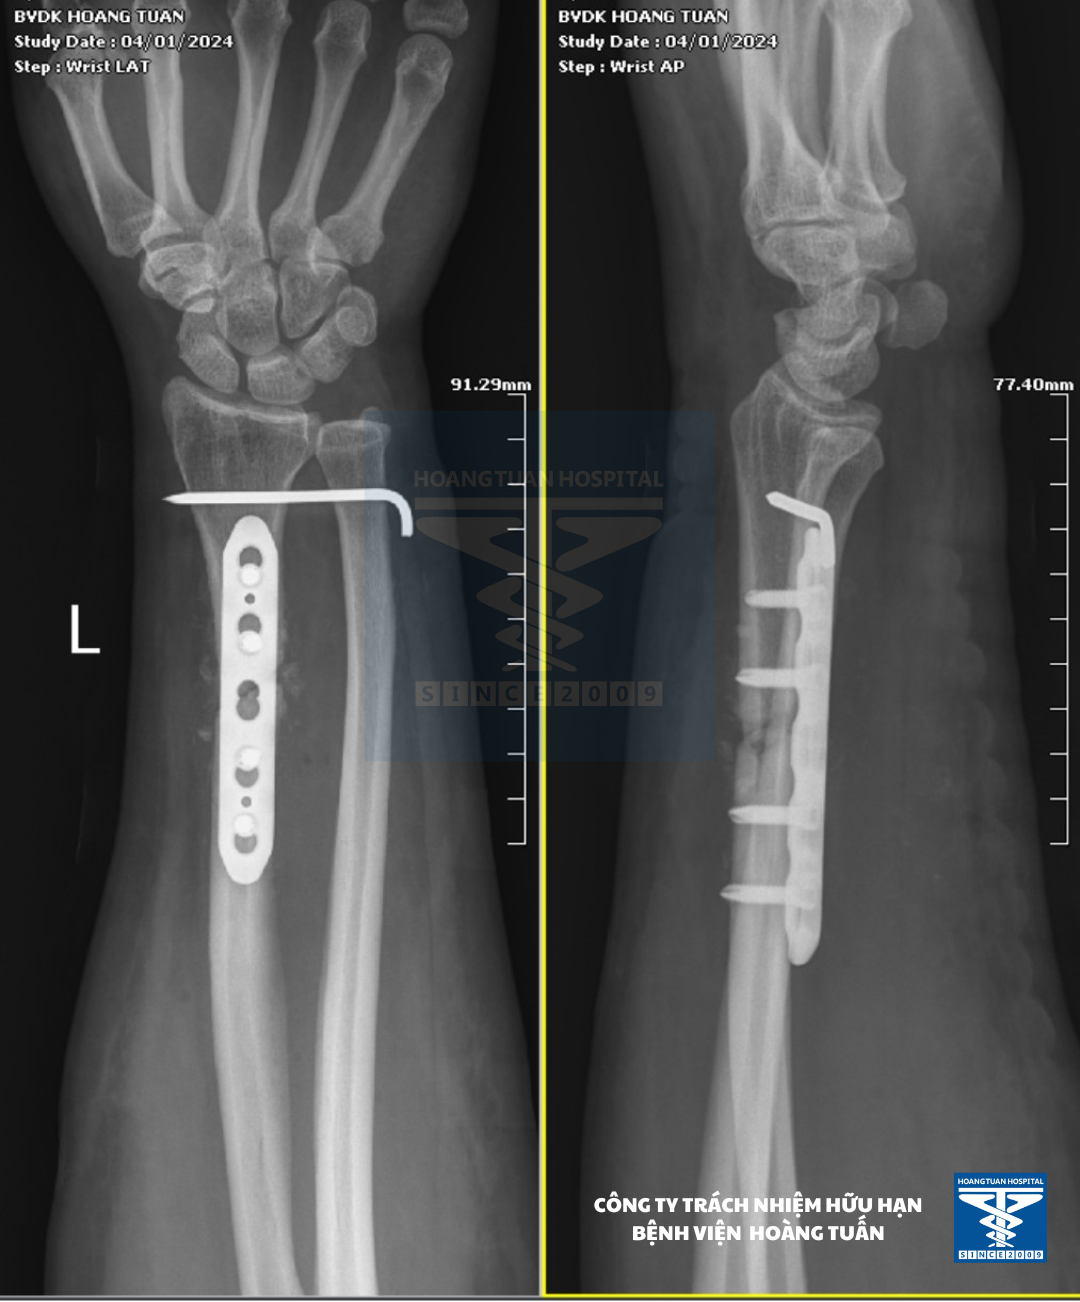

Vừa qua, vào Tháng 1 năm 2024 Bệnh viện Đa khoa Hoàng Tuấn tiếp nhận một bệnh nhân nữ 41 tuổi tự té chống vùng tay trái trực tiếp xuống đất, gãy xương vùng cẳng tay trái điều trị bó bột và đắp thuốc bắc trong 5 tuần không bớt. Đến với Bệnh viện đa khoa Hoàng Tuấn bệnh nhân được chỉ định chụp X-quang cẳng bàn tay trái, kết quả ghi nhận gãy 1/3 dưới xương quay bên trái kèm trật khớp quay trụ dưới (kiểu gãy Galeazzi). Đây là trường hợp gãy cũ “Galeazzi” và được các bác sĩ Chuyên khoa Chấn thương hội chẩn chỉ định phẫu thuật nắn trật cố định kèm kết hợp xương quay bên trái.

Sau mổ, bệnh nhân được nẹp bất động cánh cẳng bàn tay trái và được hướng dẫn tập vận động sớm tránh cứng khớp và nhanh hồi phục.

Qua 5 ngày điều trị vết mổ khô, giảm đau nhiều và bệnh nhân có thể tự cầm nắm nhẹ, bệnh nhân được xuất viện theo dõi tại nhà.

Hình 2. Hình ảnh xương cẳng tay (T) của bệnh nhân sau mổ